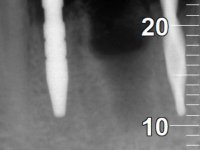

Paciente do sexo feminino com 62 anos, fumadora. 10 Anos atrás tinha sido colocado um implante na zona dos dentes 41 e 42 para reabilitar com uma ponte de dois elementos a falta destes dois dentes. Feito o exame imagiologico foi observada uma perda óssea junto ao implante compatível com uma peri-implantite. A parede óssea vestibular junto ao implante apresentava uma extensa reabsorção, estando a superfície vestibular do implante em contacto com os tecidos moles e numa determinada zona um orifício permitia a visualização do implante através do tecido gengival. Os dentes 42 e 32 apresentavam já alguma mobilidade.

Após estudo imagiológico foi planificada a colocação de dois implantes de 3.3 mm de diâmetro e 10 mm de comprimento. No dia da cirurgia foram extraídos os dentes 42 e 32 e removido o implante. Os implantes foram colocados na zona dos alvéolos tendo o cuidado de lingualizar um pouco o seu posicionamento. Foi feita uma impressão pela técnica de moldeira aberta com o retalho aberto para a confeção da ponte provisória imediata. Enquanto a impressão foi para o laboratório, foram colocados parafusos de cicatrização altos e feita a sutura da ferida cirúrgica. A paciente esperou 2 horas na sala de espera enquanto no laboratório era confecionada a ponte provisória. A ponte provisória imediata aparafusada foi colocada e o seu assentamento controlado imagiologicmente. Passados 3 meses foi realizada a impressão definitiva com uma técnica de moldeira aberta. Nessa consulta aproveitamos para polir a ponte provisória com taças de borracha para que os tecidos moles pudessem maturar em melhores condições. Foi feita a recolha de informação para caracterizar da melhor forma a estrutura monolítica em Zr. Foram utilizadas guias de cor para a cerâmica de tonalidade coronária e gengival. No laboratório foi confecionada uma ponte em Zr. aparafusada que foi cuidadosamente caracterizada. Após aprovação pela paciente foi colocada definitivamente em boca. O aperto foi feito com uma chave dinâmica com 35 N de torque. Os orifícios foram tapados com teflon e obturados com resina composta.